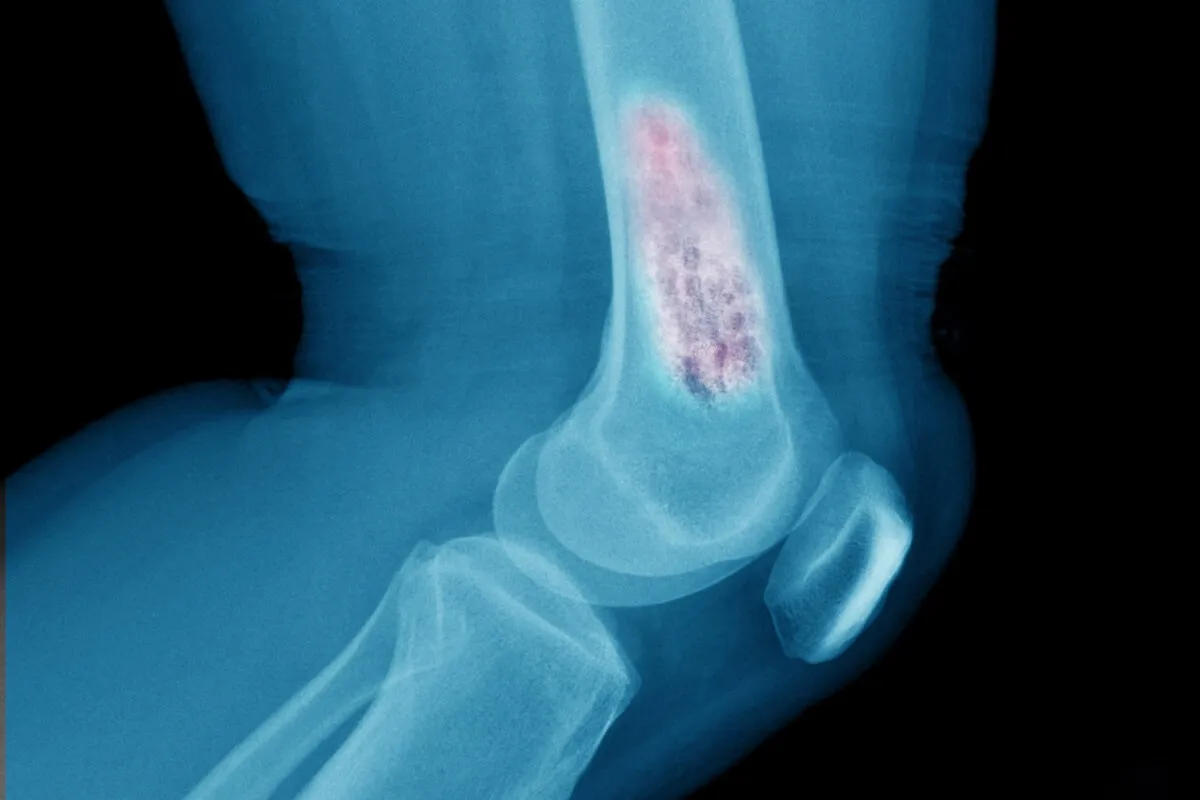

Рентгенография Костей

Рентгенография костей - это распространенный метод. Он показывает изменения в костной ткани, например, разрушение или новообразования.

Снимки помогают врачам определить признаки рака костей. Это позволяет поставить диагноз и определить дальнейшие шаги.